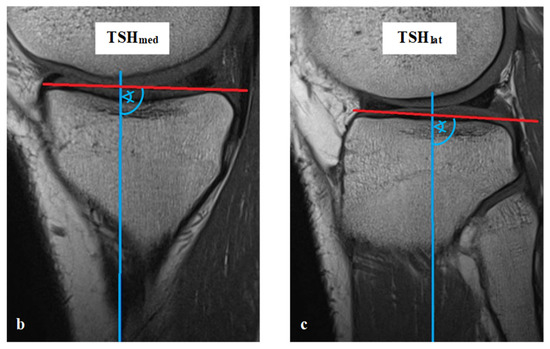

All measurements were taken via the PACS system (Picture Archiving and Communication System). Software from GE Healthcare called CentricityTM Universal Viewer was used (RA1000, edition 2019, Buckinghamshire, Great Britain). The osteoarthritis score of each knee joint was classified according to Kellgren/Lawrence (KL), in order to group patients as KJH or KJD. The TS was measured on the medial and lateral knee-joint surface according to Karimi et al. (TSKmed and TSKlat) [37] and Hudek et al. (TSHmed and TSHlat) [38]. As a reference for determining the inclination of the tibial plateau, Karimi et al. described the dorsal tibial bone cortex and Hudek et al. the tibial-shaft axis. Figure 1 and Figure 2 show the principle of the measurement methodology.

Figure 1.

Exemplary depiction of the measurements of the tibial slope according to Karimi et al. [37] for medial (TSKmed, (b)) and lateral (TSKlat, (c)) knee-joint surface: The measurements of TSK were performed in sagittal view of the knee joint in MRIs. To determine the right position of the dorsal tibial bone cortex for each TSKmed and TSKlat, a reference line was set in the best available image (a). Based on this reference line, the dorsal inclination angle of the tibial plateau was determined in the medial (TSKmed, (b)) and lateral (TSKlat, (c)) joint sections.